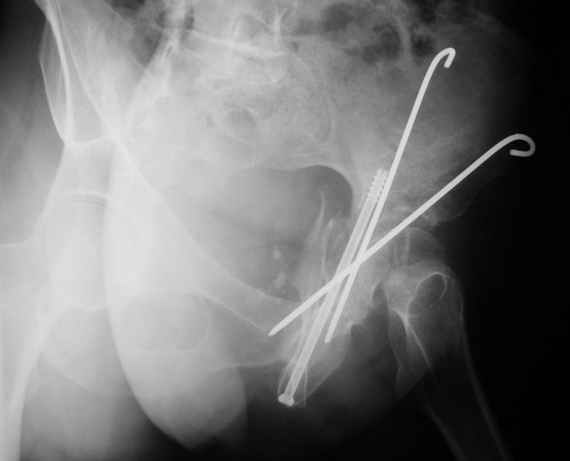

Женя! Класный перелом. Отлично репонируется изнутри таза, но лучше фиксированть сзади. Классический перелом для двустороннего доступа.

Однако есть альтернатива. Репозиция из подвздошного доступа тазовыми щипцами с разнодлинными браншами или тазовым пистолетом, а фиксация задней колонны через седалищный бугор или тазрвыми винтами 4,5 или каннюлированными 6,5 или 7,3. По-моему я посылал на ортофорум такой снимок, когда жаловался на ишемический неврит седалищного нерва через сутки после операции. Не забудь про шейку бедра - мне кажется будет хорош длинный PFN любой фирмы, какую ты найдешь, а нет так UFN + miss a nail, как это здорово делают мои земляки - Ебурбуки. Пока.

Надо сказать, что сочетание переломов вертлужной впадины + шейка + диафиз бедра - довольно редкое. Шейка+диафиз - 5% от переломов бедра, впадина + шейка = 5% от переломов впадины, а уж все три перелома...

Что интересно, при переломах шейки и диафиза бедра перелом шейки всегда с вертикальной линией. То есть фиксировать надо хорошо, и лучше с вальгизацией. Поэтому вполне приемлем и ретроградный остеосинтез диафиза бедра, а шейки - отдельно спонгиозными винтами. Если необходима операция на вертлужной впадине с отсечением большого вертела, это, наверно, наиболее практичный вариант.

Откровенно говоря, репозиция оказалась очень непростым делом, несмотря на то, что при расширенном илео-феморальном доступе все переломы как на картинке.

Сначала пытался отрепонировать смещенную заднюю колонну, но ничего из этого не получалось пока не репонировал фрагмент крыла подвздошной кости, который клином входил между отломками тела илии и задней колонной дистанция-то всего каких-то 3-5 мм, но чтобы сложить этот puzzle пришлось попотеть, я уже и дистракционные щипцы и бедренный дистрактор крутил, в конце концов все состоялось, а передняя колонна уже саморепонировалась, мне оставалось только компрессирующие винты завинтить